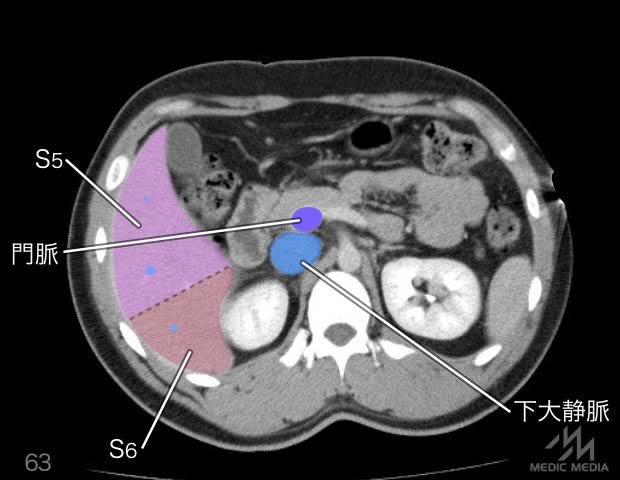

造影CT

消化器

肝区域